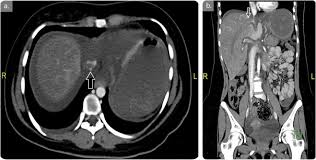

Chiasmata -mə-tə or chiasmas also chiasms 1. Esophageal varices are extremely dilated sub-mucosal veins in the lower third of the esophagus. Located in metro Denver northern Colorado and western Nebraska serving all of the Front Range our team consists of board-certified and fellowship-trained interventional radiologists. This results in hepatic congestion similar to Budd-Chiari syndrome and post-sinusoidal portal hypertension. The patients condition should be monitored throughout the procedure. They are most often a consequence of portal hypertension commonly due to cirrhosis. Toxic injury to liver sinusoids causes sloughing of endothelial cells that embolize to hepatic venules and cause eventual fibrosis of the venules. Coin in the Esophagus. There is no clear consensus regarding the number of occluded veins some authors claim that there should be at least one occluded hepatic vein 7 others state that there are no significant.

Carcinoma of the Colon. Budd-Chiari syndrome a blockage in one or more veins that carry blood from the liver back to the heart. And coumarin skin necrosis adrenal gland hemorrhage and infarction. Toxic injury to liver sinusoids causes sloughing of endothelial cells that embolize to hepatic venules and cause eventual fibrosis of the venules. Chiari malformation CM is a structural defect in the cerebellum characterized by a downward displacement of one or both cerebellar tonsils through the foramen magnum the opening at the base of the skull. Embolism and thrombosis of. La présence dune ou plusieurs affections prothrombotiques est fréquente La prise en charge repose sur un traitement anticoagulant précoce le traitement de l.